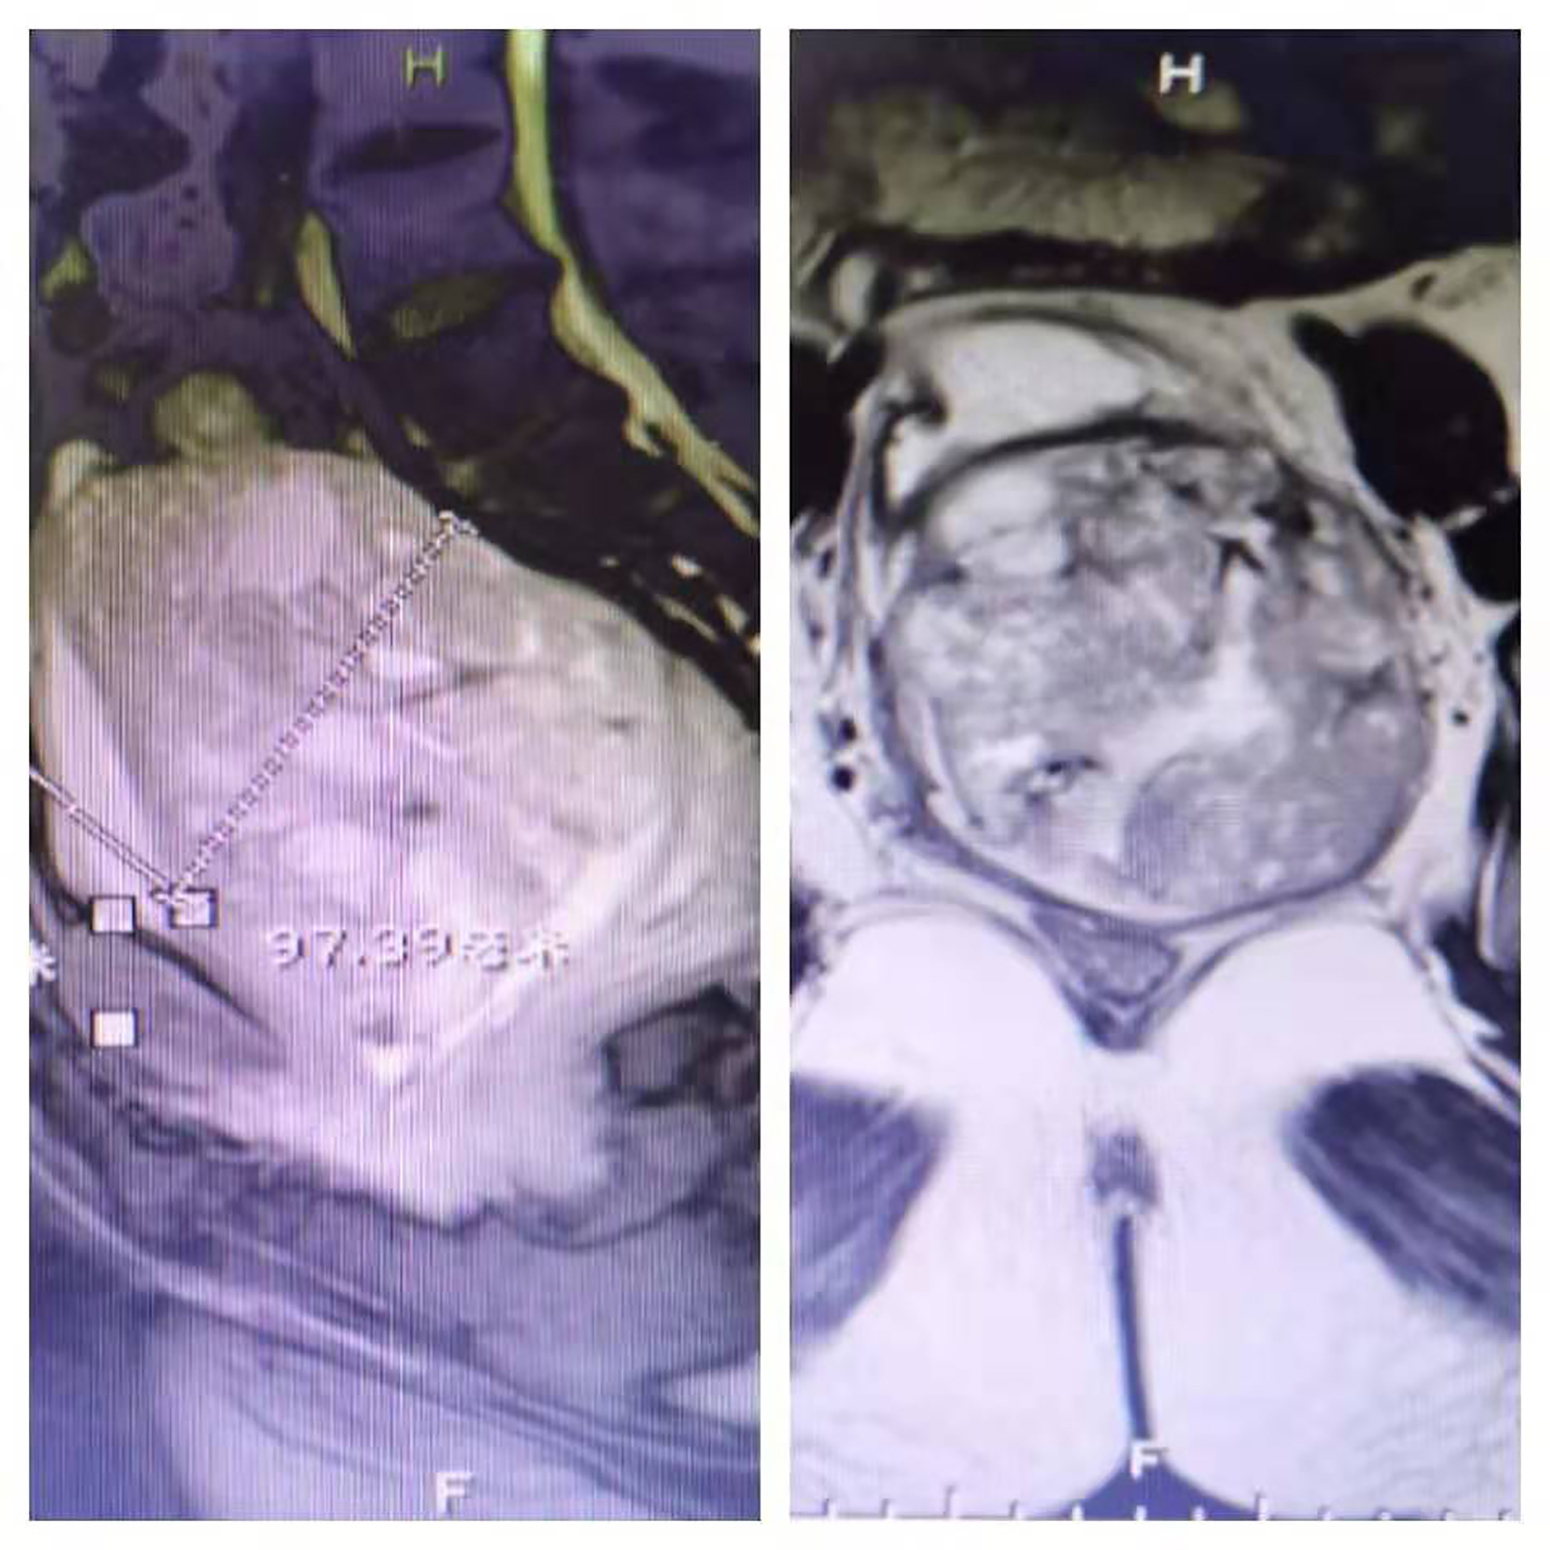

万女士紧接着说:“2019年8月5日,我们有幸被人指点说京东中美医院肿瘤二科的郑里主任‘招数’多,就急忙赶来了。见到郑里主任,她全面了解了我的病情,先行请全院多学科会诊,意见是我的体能还可以,由郑主任全面决策优化治疗方案;8月9日下午3点,为我施行了‘盆腔巨块肿瘤多支供血动脉灌注化疗术+栓塞术’,没想到肿瘤一下子就减小了很多,我的‘尿袋’也终于可以甩掉了...”

图片:患者肿瘤术前(左)和术后(右)对比

2019年的国庆节期间,万女士和老伴儿终于如愿以偿的参加了儿子的结婚典礼,而且是体面的不带“尿袋”的出席,这一天,她等的太久了,等的太辛苦了,等的太煎熬了;然而,这一天也真的等来了...

2019年10月30日,已在中美医院行第3次介入联合靶向治疗,万女士不仅实现了“愿望”,而且困扰多年的贫血症状也有了改善,精气神都有了改观。为了感谢郑里主任的“救命之恩”,她和老伴儿特意订做了一面锦旗送给郑里主任和京东中美医院肿瘤二科的全体医护人员。